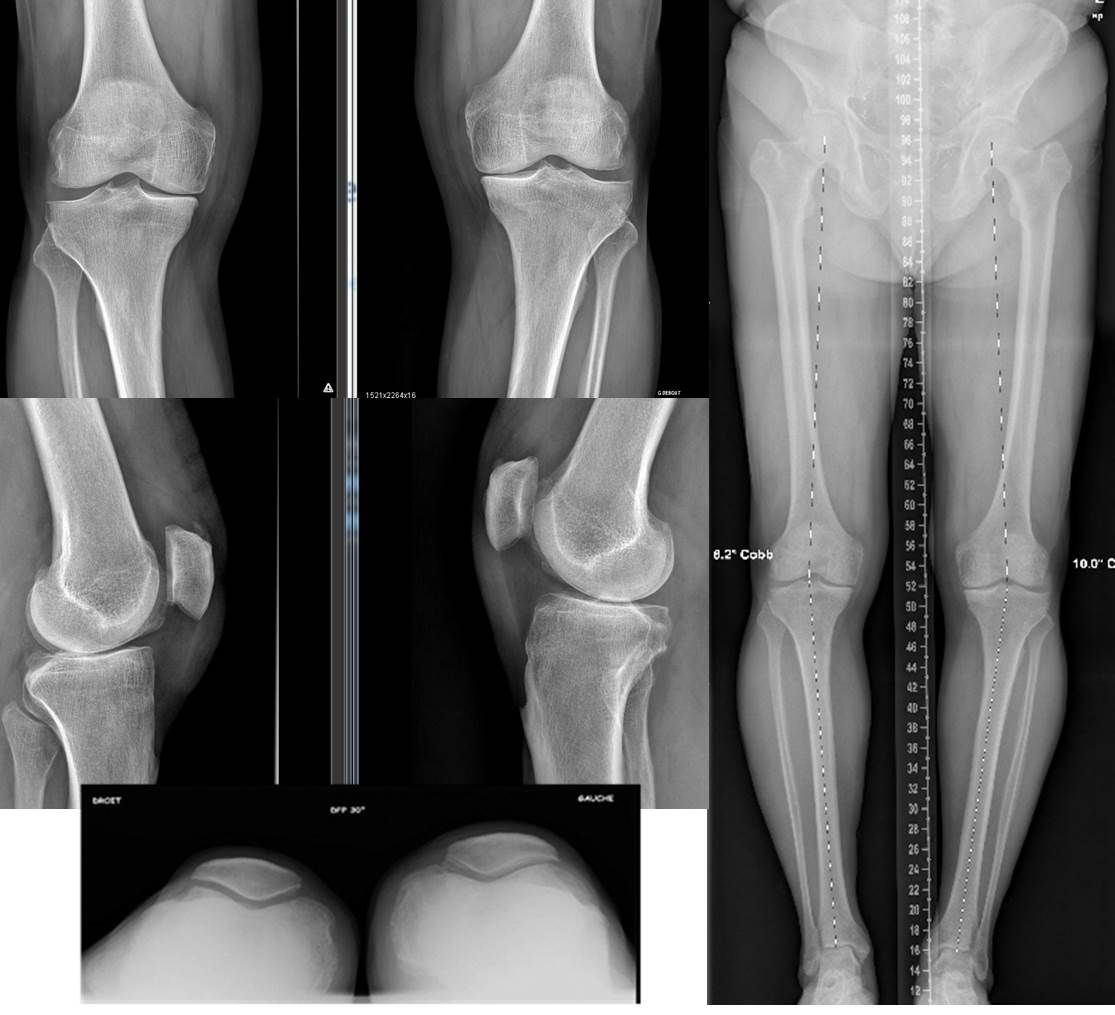

Technique Prothèses unicompartimentaires bilatérales en un temps : Technique opératoire et revue systématique de la littérature , Nicolas Pujol Centre Hospitalier de Versailles, 177, rue de Versailles, 78157 Le Chesnay, France 🖂 npujol@ch-versailles.fr , Alexandre Abitan Centre Hospitalier de Versailles, 177, rue de Versailles, 78157 Le Chesnay, France , Cyrille Lallemant Centre Hospitalier de Versailles, 177, rue de Versailles, 78157 Le Chesnay, France , Jean-François Taburet Centre Hospitalier de Versailles, 177, rue de Versailles, 78157 Le Chesnay, France , Philippe Boisrenoult Centre Hospitalier de Versailles, 177, rue de Versailles, 78157 Le Chesnay, France , Camille Steltzlen Centre Hospitalier de Versailles, 177, rue de Versailles, 78157 Le Chesnay, France N°296 - Août / Septembre 2020 ● 13 min de lecture